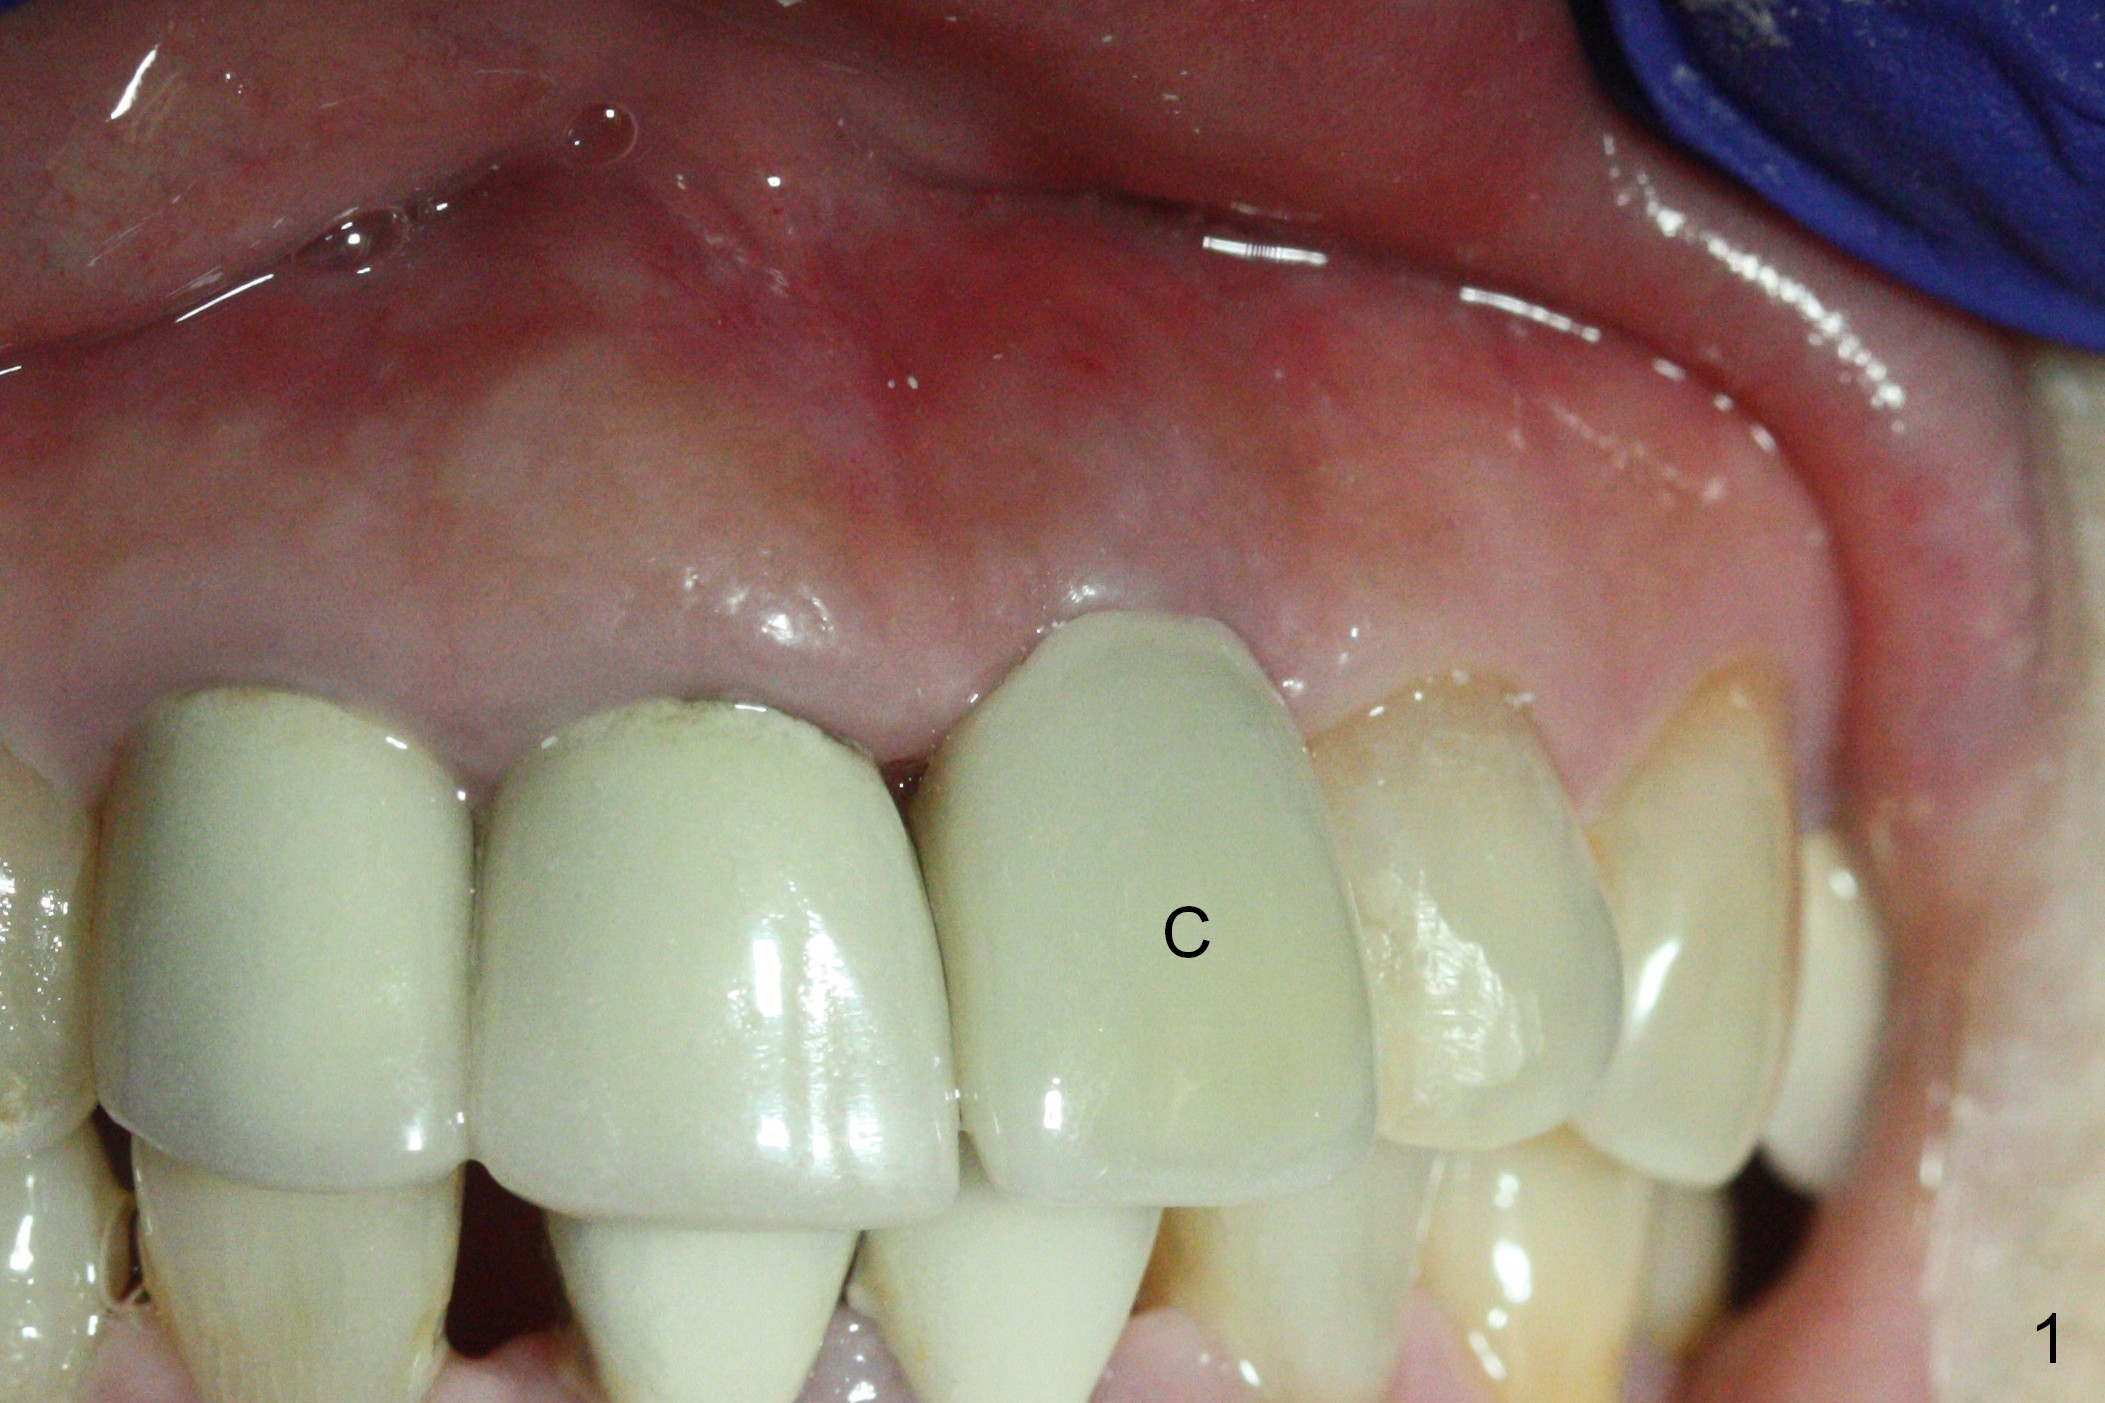

When a permanent crown (Fig.1 C) is seated 5 months postop, it looks too long and bulky (as well as metal show through cervically), which is in turn due to buccal placement of the crown (Fig.2) and abutment (Fig.3). By mistake, abutment is changed from 4.5x15°, 3 mm cuff to 4.5x15°, 2 mm cuff (Fig.4-6); the profile appears to improve. After prep (buccoincisal (Fig.4 ^) and linguoincisal), impression is taken. The gold coating in the buccocervical area is untouched so that there should be no or minimal metal show through. Please make a new crown as cosmetic as possible (not too bulky, especially buccocervical). If you feel that the result will be the same as before, return the case. The angled abutment may be changed 25°. In fact the new crown looks better.